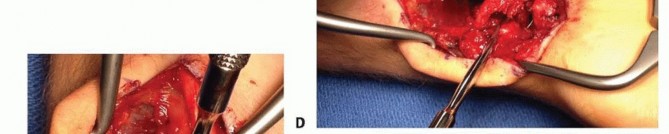

Graft Harvest and Inset

With the dimensions of the scaphoid defect known, the surgeon returns to the distal radius to harvest the graft. The previously isolated 1,2 IC SRA pedicle is traced proximally to the planned harvest site on the dorsal metaphysis of the distal radius. Using a fine sterile marking pen, a rectangular or trapezoidal cortical window is mapped out, ensuring that the distal insertion of the 1,2 IC SRA pedicle is perfectly centered within the planned bone block.

The osteotomy is performed using extremely sharp, fine osteotomes or a precise microsurgical saw. The cuts must be made with delicate, controlled taps to avoid fracturing the fragile cortical shell of the graft. The osteotomes are